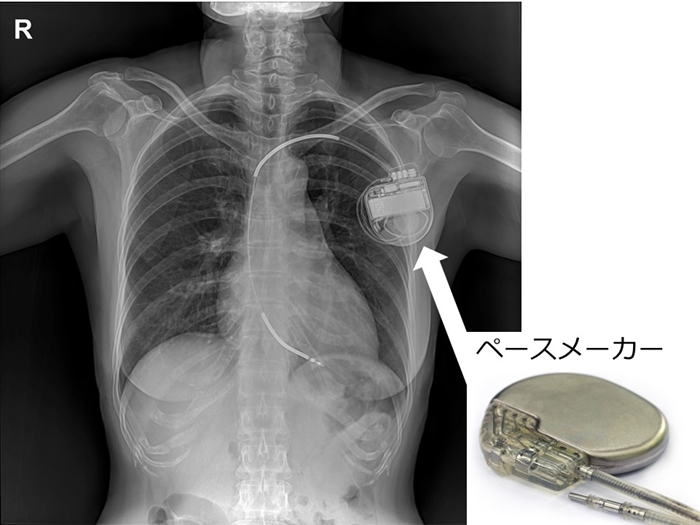

ペースメーカー本体や電極自体は

MRIの撮影に耐えられる材質でも、

心臓MRIの撮影を実施するには

様々な条件があり,

簡単には実施しにくい実情があります。